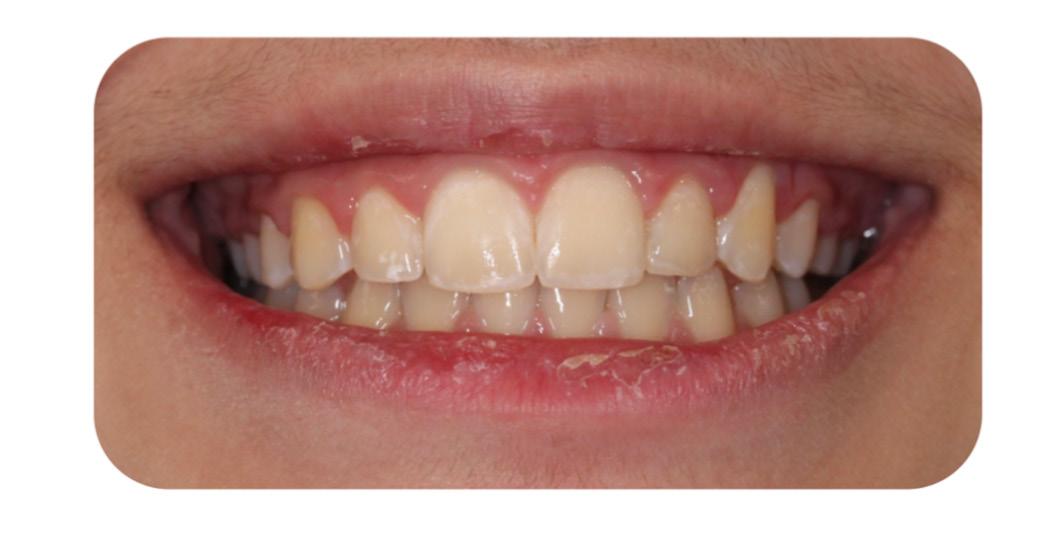

After re-bracketing, the treatment continued with the progression of the arch wires: a .014 NiTi, a .018 NiTi, a .019x025 “V” Force -3 and the final arch wire a .018x.025 SS. These final arch wires were left for three months. After this time, the esthetics, TMJ, airway, occlusion and alignment were evaluated. The patient reported that he was satisfied, and very happy with the result (Figure 11-A, B, C, D, E, F).9

FIG. 11C: Pre-de-bracketing, lips in repose

FIG. 11D: Pre-debracketing, posed smile

Fig. 13H: Post-treatment, posed smile

Fig. 13K: Post-treatment, posed smile Text